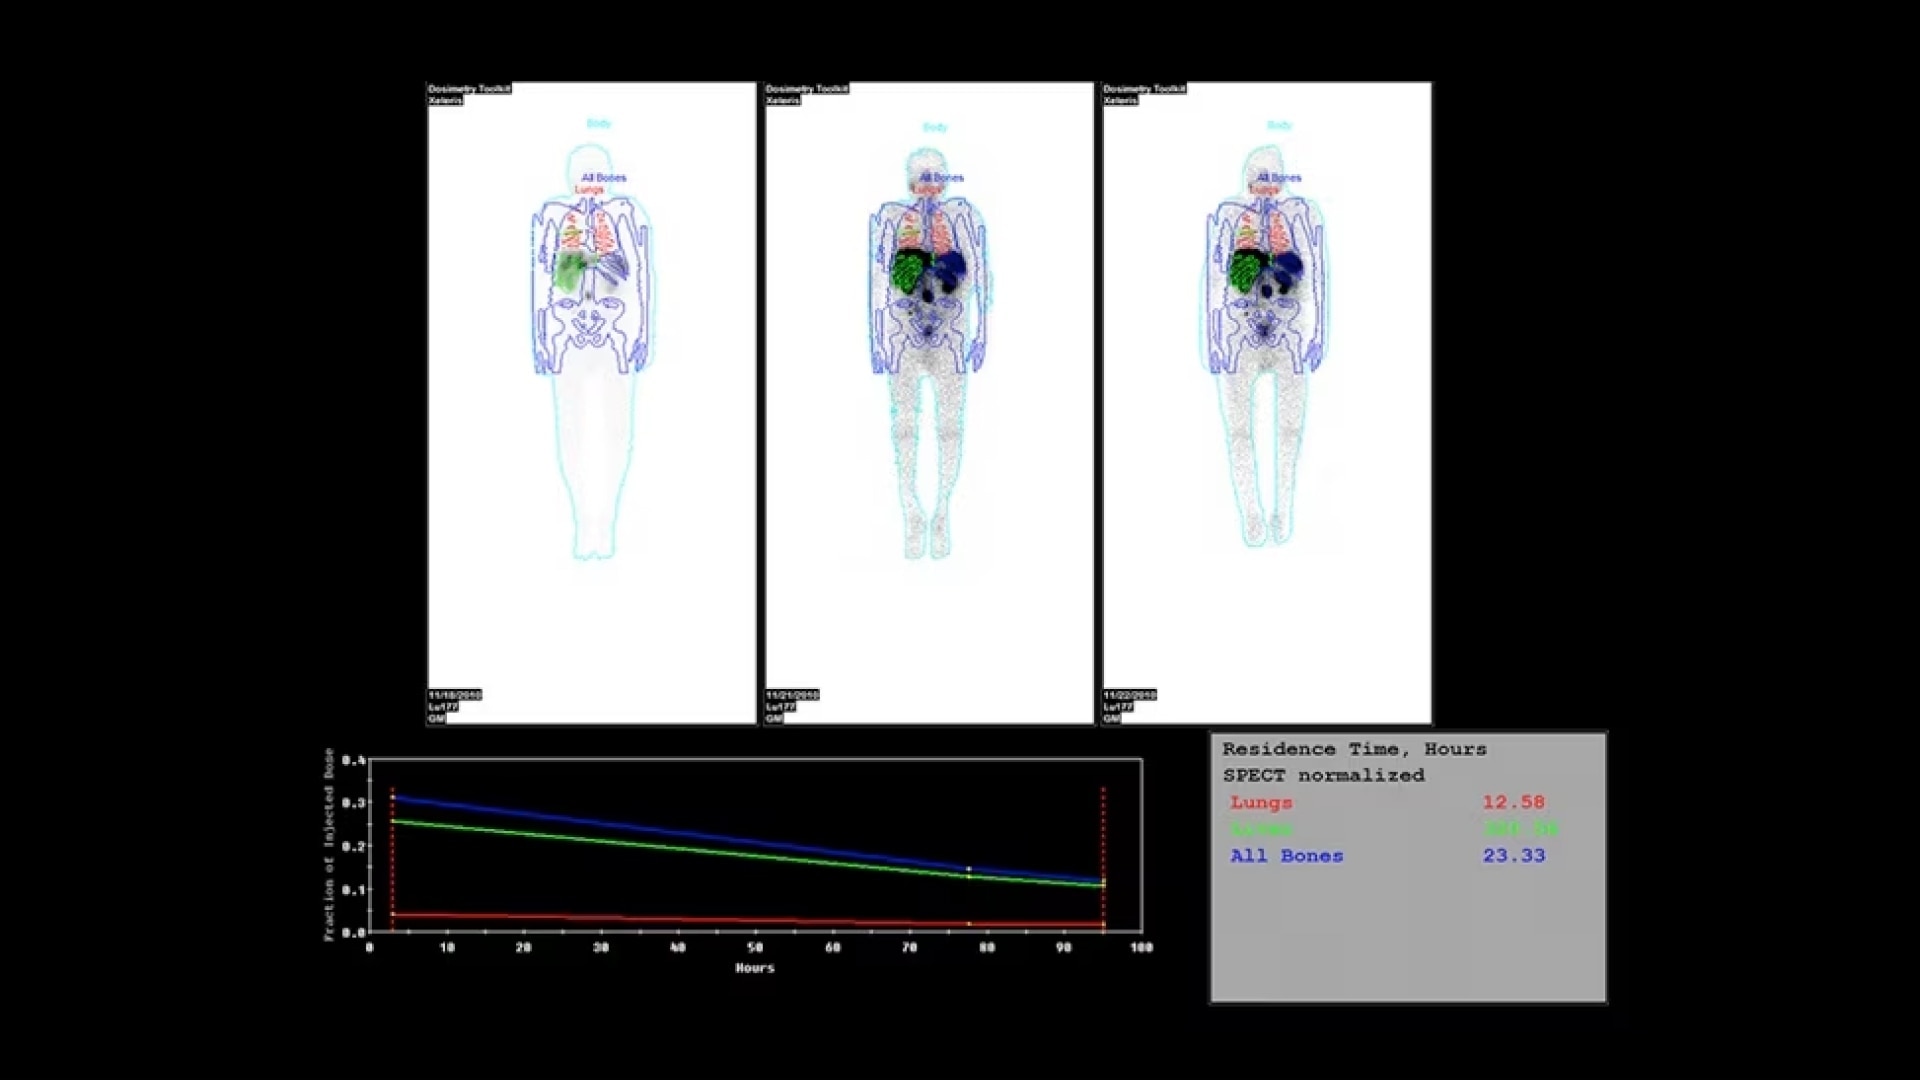

A fully digital vision for nuclear medicine

A fully digital vision for nuclear medicine

Additionally, this is a premium SPECT/CT system that delivers the added flexibility of a standalone CT that includes advancements in dose and metal artifact reduction. And it delivers the accurate, reproducible results referring physicians require in a comfortable and streamlined exam experience.